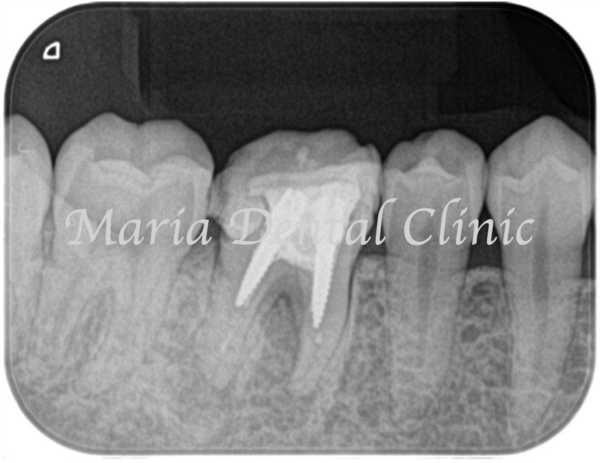

歯周組織再生療法3ヶ月後には分岐部(歯の股の部分)に確認されていた歯周病(術前写真)は完全に治癒していることを確認しました(術後3か月写真)。また同時に、術前に確認できた根尖性歯周炎も綺麗な治癒が確認できたことから最終補綴処置へ移行しました。今後最低2年間は歯肉、根尖周囲組織の治癒経過を患者様にご協力いただき確認していく予定です。